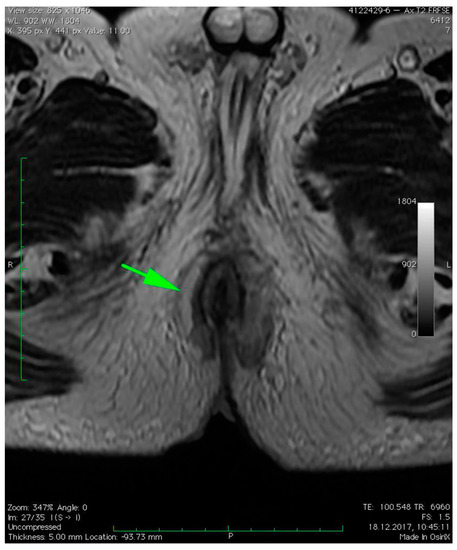

3. Case Presentation